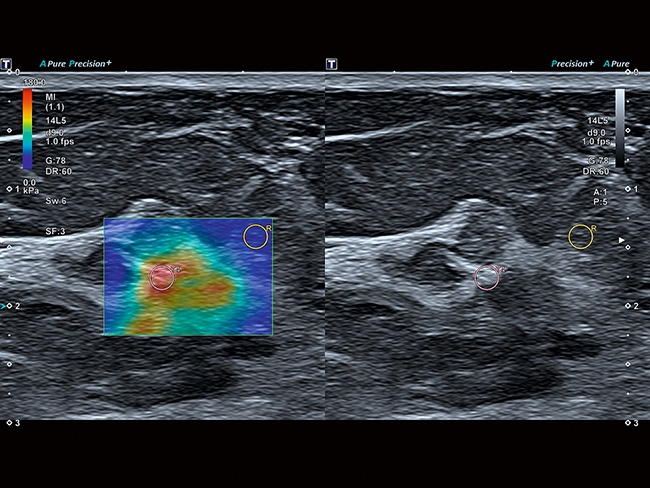

• MicroPure. Высокотехнологичное решение в области выявления микрокальцификатов – маркеров новообразований злокачественного типа. Маркеры идентифицируются путем изучения затененных изображений целевого участка. Микрокальцификаты отображаются в виде белых пятен.

• SMI. Опция, упрощающая визуализацию микроциркуляторного русла. С ее помощью обследуются сосуды с низкой интенсивностью кровотока, изучаются наиболее тонкие структуры. SMI упрощает диагностику новообразований, минимизирует вероятность ошибки.